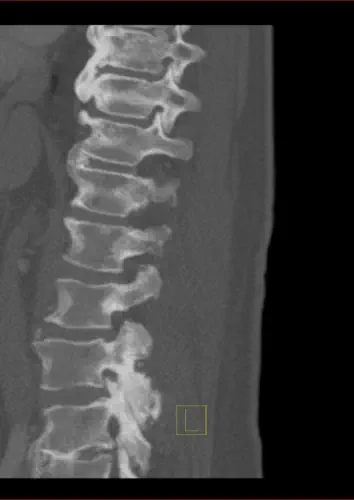

MRT und CT - Bilder - Auswahl

Osteoplastische Knochenmetastasen zeichnen sich dadurch aus, dass Krebszellen den Knochen angreifen und eine übermäßige Bildung von neuem Knochengewebe anregen, was zu einer Verdichtung und Sklerosierung des Knochens führt. Die jedoch die Knochenstabilität nicht verbessert. Die im Gegensatz zu Osteolytische Metastasen bei denen Knochen abgebaut wird. (Zum Beispiel Löcher, dünne Knochen und dünne Knochenränder)